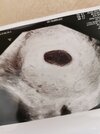

Ciąża 6/7 TC brak zarodka

Witam, dziś byłam na wizycie (2 już) u ginekologa. Pęcherzyk ciążowy ma już 2 cm, a nie ma zarodka, w zeszłym tygodniu pojawiła się obręcz pęcherzyka żółtkowego, dziś pęcherzyk ciążowy ma już 2 cm ale zarodka brak,nie ma już nawet pęcherzyka żółtkowego. We wtorek mam mieć kolejna wizytę, jestem załamana. Miesiączkę miałam 6 lutego, a owulacje 21 lutego, czy mogę mieć jeszcze nadzieję? Bo lekarz powiedział że jest 1 procent szans..

• 16166760497687518172698059903406.jpg